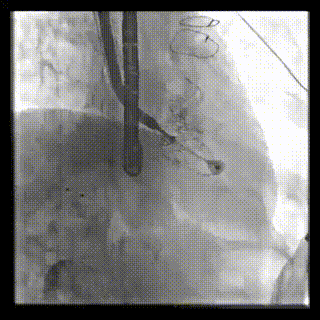

2021年12月24日,復旦大學附屬中山醫院葛均波院士團隊成功應用LuX-Valve Plus為一例極重度三尖瓣反流(TR)合并房顫、房缺的患者完成了經血管三尖瓣置換術,這是在前基礎上,本周完成的第三例經血管三尖瓣置換手術,葛均波院士、周達新教授等與心外科魏來教授、賴顥教授,心超室的潘翠珍教授、李偉教授及麻醉科的郭克芳教授共同完成了本周手術,均獲得圓滿成功!患者術后超聲顯示無TR,臨床癥狀明顯改善。本周手術的成功也為LuX-Valve Plus救治性臨床研究添上了濃墨重彩的一筆。

本周三例接受LuX-Valve Plus經血管三尖瓣置換術的患者中,第一例患者為冠狀動脈旁路移植術+Bentall+二尖瓣成形術后;第二例患者為永久起搏器植入術后,存在跨三尖瓣導線;第三例患者合并房顫、房缺及左心耳封堵術后。

三例患者入院后,葛均波院士團隊周達新教授、潘文志教授、張源博士、陳莎莎博士及心超室的潘翠珍教授、李偉教授對患者的情況進行詳細評估和討論,最終決定為三例患者選擇LuX-Valve Plus40mm、50mm和50mm型號的瓣膜進行手術治療。手術后即刻拔除氣管插管,術后患者三尖瓣反流癥狀得到顯著改善,復查心超結果顯示人工三尖瓣瓣膜支架固定穩定,瓣葉關閉形態未見異常,未見明顯反流。